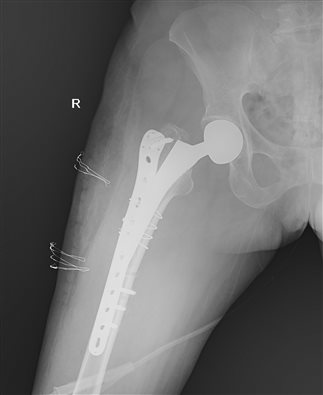

苏纯柱主任向患者家属介绍治疗方案,建议手术治疗。患者入院后,苏纯柱主任召开科室病例讨论,研究患者的治疗方案。结合患者身体状况,考虑患者可以耐受手术。入院第三天,在麻醉科、手术室的大力配合下,手术顺利进行,手术历时2小时,术后患者恢复良好。患者及家属对手术治疗效果非常满意。

苏纯柱主任介绍随着人口老龄化及人工关节的普及,假体周围骨折的数量逐年上升,由于患者多为老年人,伴有骨量减少、骨质疏松、骨质丢失严重;假体周围骨折的治疗比较复杂。本例患者髋关节置换术后3周,结合拍片考虑患者假体稳定,因此不需要处理髋关节假体,仅行假体骨折固定即可达到满意效果。